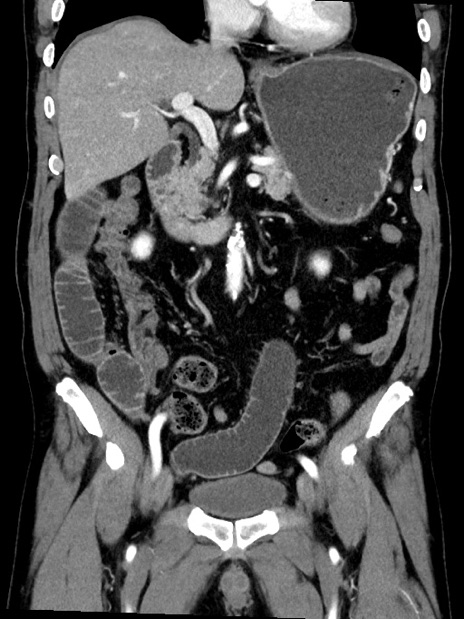

症例35(冠状断像)

【症例】70歳代 男性

【主訴】腹部膨満、嘔吐

【現病歴】昨日より腹部膨満感出現。本日増悪し、仙痛出現。嘔吐あり、受診。

【既往歴】糖尿病、胆摘後

【身体所見】BP 149/80mmHg、HR 74/min、BT 35.9℃、腹部:膨満、軟、圧痛なし。腸雑音減弱あり。上腹部正中切開瘢痕あり。

【データ】WBC 13500、CRP 1.72